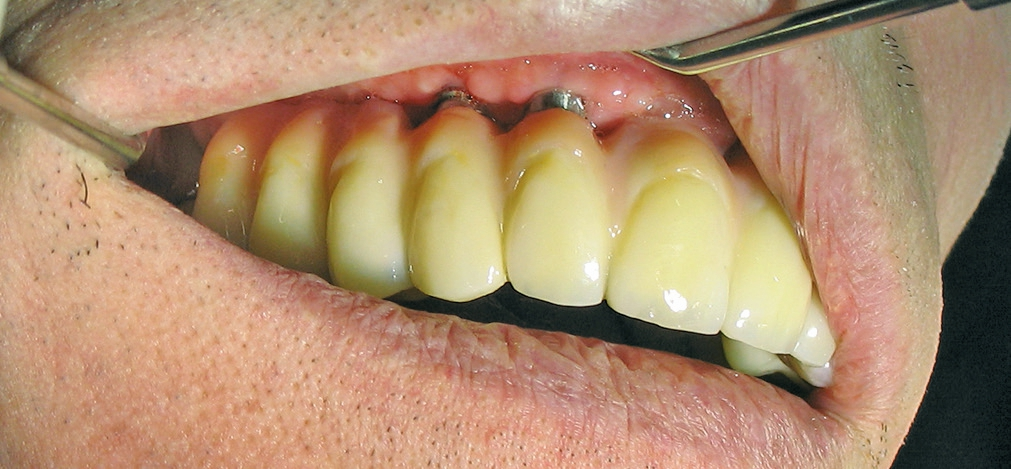

Für die Suprakonstruktionen wurde das Sekundärgerüst auf Abutment-Niveau gefräst. Der Patient bekam im Oberkiefer ein System mit interner Sechskantverbindung (Abb. 9-16). Die Patientin im Unterkiefer bekam ein System desselben Herstellers mit konischer Abutmentverbindung (Abb. 1-8). Davon ist ein Implantat noch in der Einheilphase verloren gegangen. Der betroffene Kiefer konnte trotzdem mit fünf Implantaten versorgt werden. Vom Prinzip „all-on-4“ wurde bewusst Abstand genommen. Ebenso wurde auch auf geneigt gesetzte Implantate verzichtet. Die Implantate, die abgewinkelte Abutments bekamen, wurden nach den prothetisch und anatomisch günstigsten Knochenverhältnissen gesetzt.

Bei allen Systemen waren die abgewinkelten Abutments zweiteilig; Abutment und Halteschraube. Die geraden Abutments waren einteilig. Das Einbringen der zweiteiligen Komponenten ist aufwändig und kann einiges an Zeit kosten. Alle Komponenten hatten einen Rotationsschutz und waren sowohl mit konkavem als auch mit konvexem Austrittprofil für die Sechskantverbindung. Durch die konkave Gestaltung des Emergenzprofils wird dem Weichgewebe Platz geboten. Dieser Platz reduziert einerseits die Gefahr von Rezessionen (Pseudorezessionen durch zu hohen Druck am Zahnfleisch vestibulär) und formt zugleich eine Zahnfleischmanschette um den Implantathals. Letzteres schützt den krestalen Knochen und verhindert das Durchschimmern der grauen Titanoberfläche.